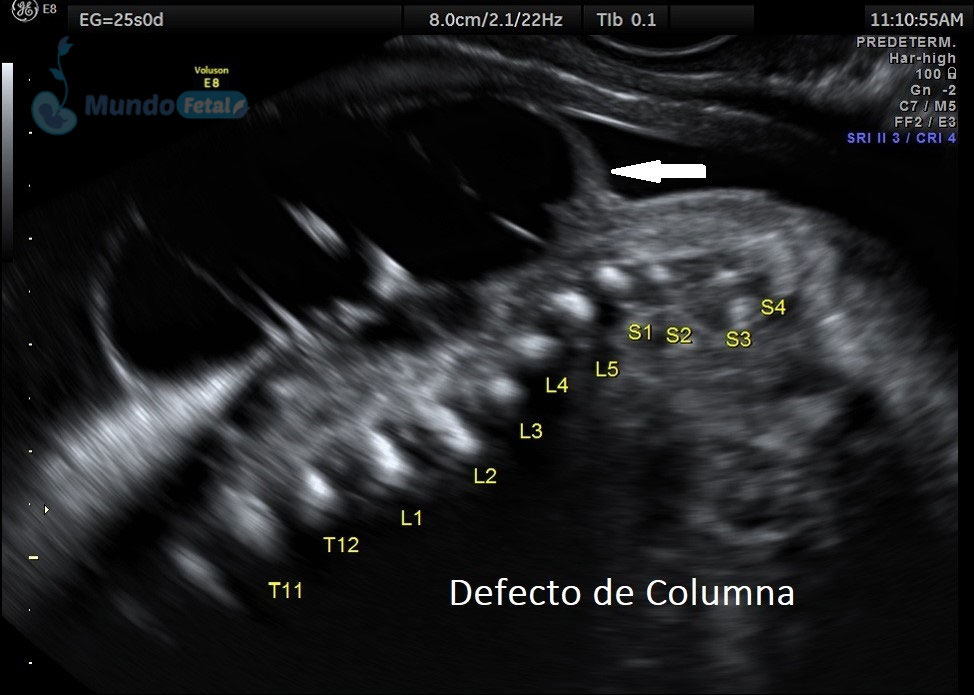

Ultrasonido Nivel II, Patología Fetal

Estudio llevado a cabo en todo bebe, en quien se haya detectado alguna alteración anatómica o marcador de riesgo, valorando todos sus órganos, aparatos y sistemas, de manera específica y detallada.